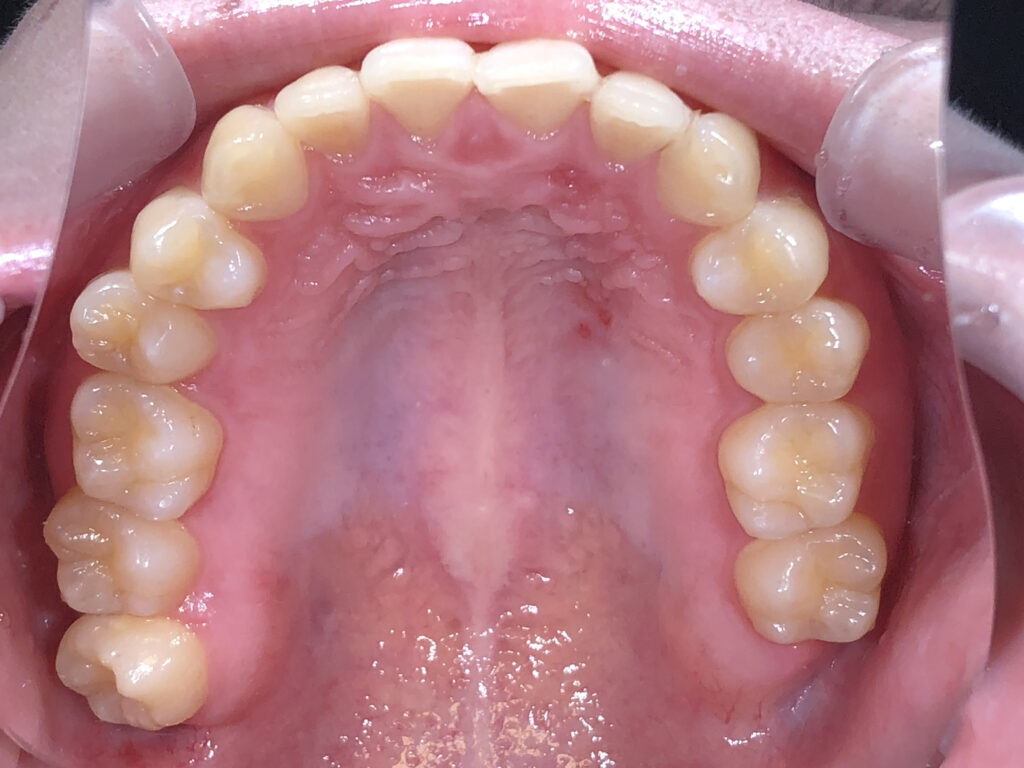

上顎

治療前